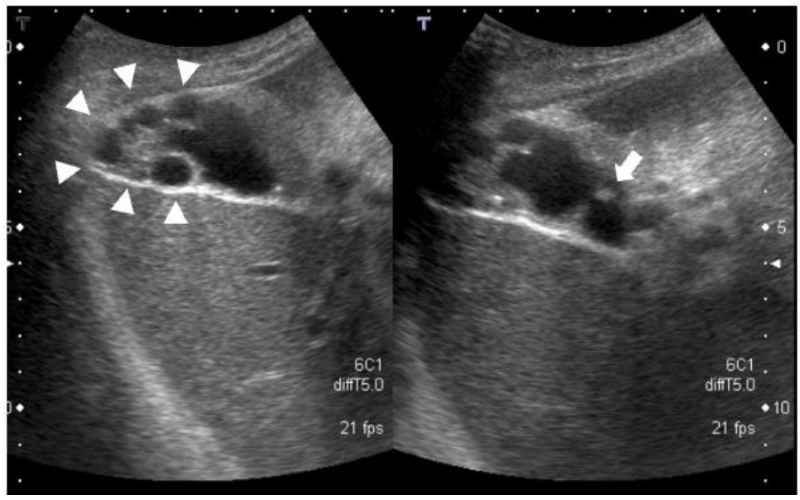

Siêu âm là một trong những phương pháp thường được sử dụng đầu tiên để phát hiện u cơ tuyến túi mật. Khi khảo sát, bác sĩ sẽ tìm kiếm một số dấu hiệu đặc trưng như:

- Thành túi mật dày lên, thường khu trú ở một đoạn thành túi mật.

- Xuất hiện xoang Rokitansky – Aschoff (các túi nhỏ nằm trong lớp thành túi mật).

- Có thể thấy hiện tượng “đuôi sao chổi” (comet-tail artifact) – Dạng phản xạ đặc trưng của sóng siêu âm do các tinh thể cholesterol hoặc cặn mật nằm trong các xoang này.

Những dấu hiệu này giúp gợi ý chẩn đoán u cơ tuyến túi mật (adenomyomatosis) và hỗ trợ phân biệt với một số tổn thương khác của túi mật.